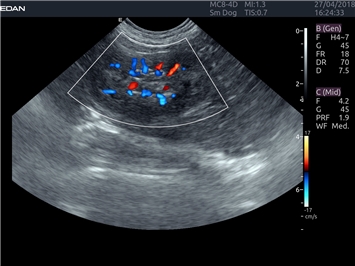

EDAN Acclarix LX4 VET

EDAN Acclarix LX4 VET представляет собой профессиональную ультразвуковую систему, специально разработанную для ветеринарных исследований. Сочетание стабильности, высокой производительности и эффективности делает эту систему идеальным выбором для современной ветеринарной практики.

Энергетический допплер:

Да

Цветовой допплер: